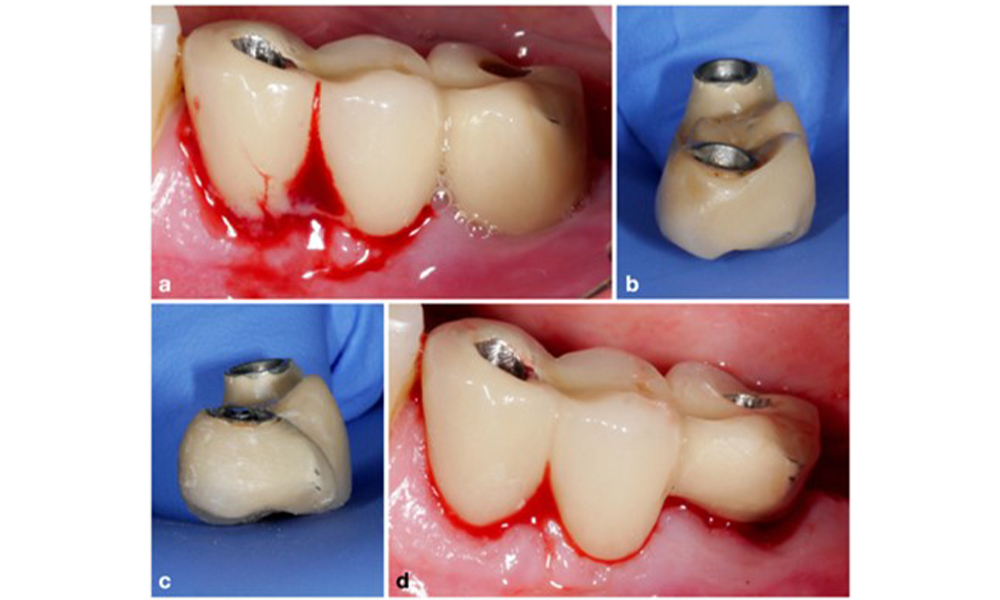

Patientenfall mit Periimplantitis. Die nicht-chirurgische Behandlung erfolgt mit dem supragingivalen (a-b) und subgingivalen Handstück eines Luftpoliergeräts (c-d). Durch Abnehmen der Suprakonstruktion lässt sich ein besserer Zugang zur Implantatoberfläche erzielen (d).

Abb. 9. Patientenfall mit Periimplantitis. Die nicht-chirurgische Behandlung erfolgt mit dem supragingivalen (a-b) und subgingivalen Handstück eines Luftpoliergeräts (c-d). Durch Abnehmen der Suprakonstruktion lässt sich ein besserer Zugang zur Implantatoberfläche erzielen (d).